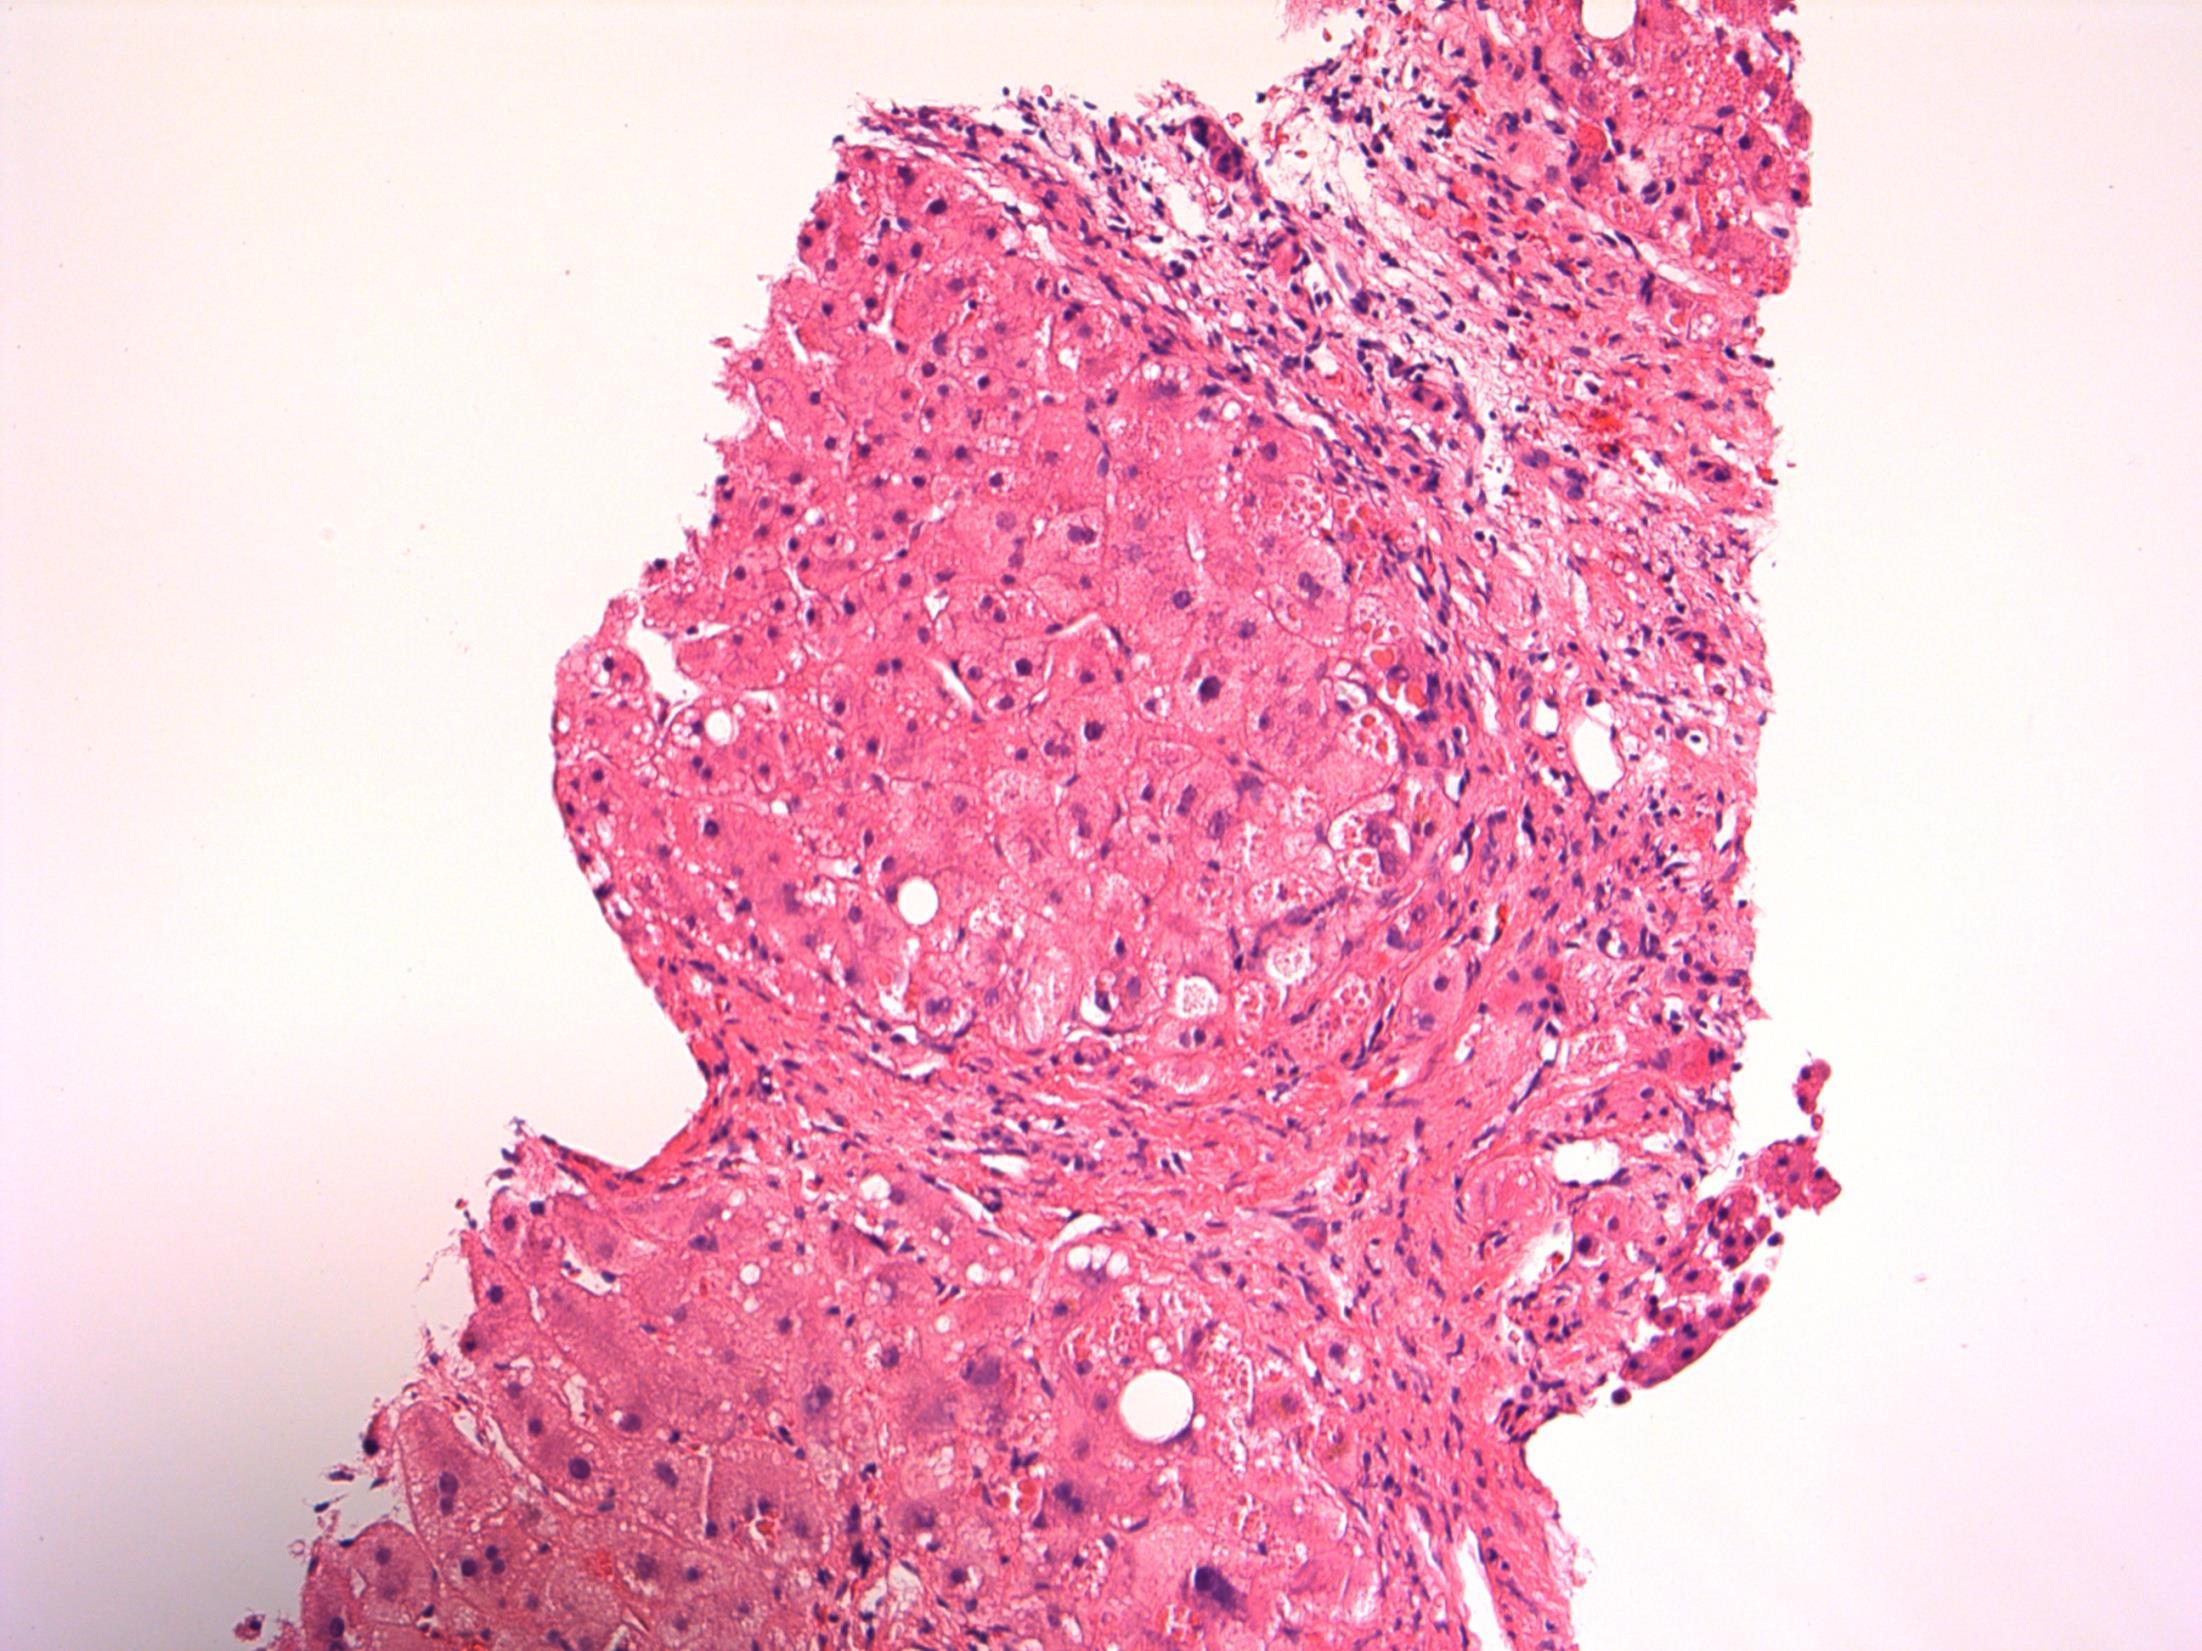

Cirrhosis with alpha 1 antitrypsin deficiency

Description: Nodules of hepatocytes surrounded by fibrovascular septae. There is ductular reaction and inflammation of varying degrees. Mild steatosis. Also oval cytoplasmic eosinophilic globular inclusions in periportal hepatocytes.

Diagnosis: Cirrhosis with alpha 1 antitrypsin deficiency.

Plan: Liver special stains: A-1 AT – PAS+, diastase resistant, globules in hepatocytes. IHC to A-1AT to confirm.

Correlate with any clinical history of A-1AT lung disease (patient has breathlessness).

Correlate with LFTs, radiology, previous biopsies .

Comments:

PiZZ genotype. Increased risk of HCC